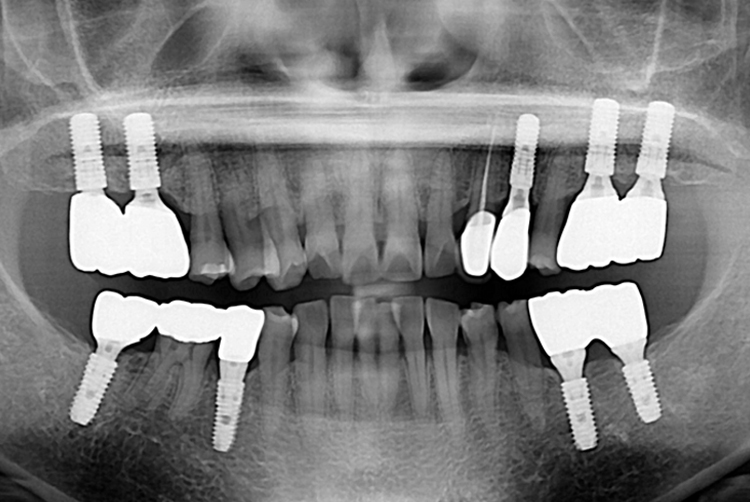

[임플란트] 임플란트

b89ef53802a870b3b68993af93caa982.jpg

치료전 : 2019-08-14

세종치과는 많은 환자와 다양한 케이스를 바탕으로 항상 편안한 임플란트 수술을 제공하고자 노력하고,

오래동안 튼튼히 쓸 수 있는 임플란트 수술을 가장 큰 목표로 삼고 있습니다